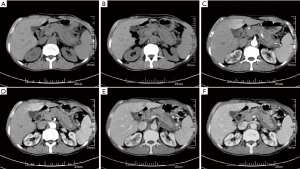

Comparison of CT scan results between the 2 groups revealed that in the PC group, the density of the lesions on the CT scan was mostly decreased, the pancreas was not swollen, and the kidneys were not involved. The bile duct wall was thickened, of sausage-like appearance, and envelope-like edges were rare. The blood vessels were invaded, lymph nodes were enlarged, and the pancreatic duct was truncated. The AIP group was just the opposite (Figure 1A,B). The difference in the proportion of the abovementioned CT features between the 2 groups was statistically significant (P<0.05), see Table 2.

Comparison of CT imaging features between the 2 groups showed that the shape of the lesions in PC patients was mainly spherical, of uniform density, and the enhanced scan was mainly low-density, whereas the shape of the lesions in the AIP group was mainly long, of uneven density, and the density of the enhanced scan was moderately high (Figure 1C,D,E,F). The difference in morphology and density between the 2 groups was statistically significant (P<0.05), see Table 3.